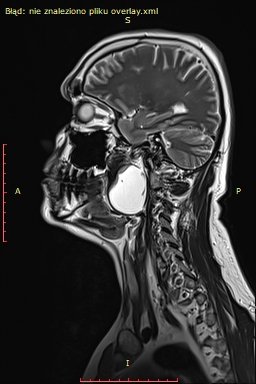

Wielki sukces lekarzy z Oddziału Chirurgii Głowi i Szyi i Chirurgii Robotycznej Szpitala Morskiego im. PCK w Gdyni! Przeprowadzono tam z sukcesem operację usunięcia guza przestrzeni przygardłowej u 48-letniego pacjenta. Zabieg wykonano z wykorzystaniem nowoczesnej technologii chirurgii robotycznej. Pacjent czuje się świetnie! Ta historia zaczęła się bardzo źle. Badanie rezonansu magnetycznego wykazało u 48-letniego pacjenta gdyńskiego szpitala obecność dużej zmiany torbielowatej w przestrzeni przygardłowej po stronie lewej o wymiarach 54x42x38 mm. Zmiana miała postać torbieli zawierającej jednolity płyn, z pogrubiałą, postrzępioną wewnętrzną ścianą i gładką powierzchnią zewnętrzną. Torbiel powodowała przemieszczenie i ucisk okolicznych struktur. Biopsja aspiracyjna cienkoigłowa sugerowała torbiel boczną szyi.Gdyńscy lekarze zdecydowanili się na zastosowanie nowoczesnej technologii chirurgii rozbottycznej. Zabieg przeprowadzono drogą przezustną – po nacięciu przedniego łuku podniebiennego po stronie lewej, uwidoczniono torbiel, którą następnie precyzyjnie oddzielono od otaczających tkanek i usunięto w całości. Ranę w jamie ustnej zamknięto szwami. Operację przeprowadził dr n.med. Dariusz Nałęcz wraz z zespołem lekarsko-pielęgniarskim. Pacjent został wypisany do domu już następnego dnia po zabiegu w dobrym stanie ogólnym i miejscowym, nie zgłaszając istotnych dolegliwości. Samodzielnie przyjmował pokarmy stałe. – mówi dr n. med. Dariusz Nałęcz. - W tym tygodniu pacjent ponownie odwiedził Oddział Chirurgii Głowi i Szyi i Chirurgii Robotycznej Szpitala Morskiego im. PCK w Gdyni, gdzie kontrolne badania pooperacyjne potwierdziły prawidłowy przebieg gojenia. Badanie histopatologiczne potwierdziło, że usunięta zmiana była gruczolakiem podstawnokomórkowym rosnącym w formie torbieli, bez naciekania ściany i całkowicie usuniętym w granicach tkanek zdrowych. Zabieg jest przykładem skutecznego wykorzystania technologii chirurgii robotycznej w leczeniu skomplikowanych przypadków w trudno dostępnych lokalizacjach anatomicznych, zapewniając jednocześnie szybki powrót pacjenta do zdrowia i minimalizując ryzyko powikłań – dodaje dr n.med. Sławomir Piotrowski, ordynator Oddziału Chirurgii Głowi i Szyi i Chirurgii Robotycznej Szpitala Morskiego im. PCK w Gdyni. Gratulujemy lekarzom, a pacjentowi życzymy dużo zdrowia! Galeria zdjęć Pobierz galerię Przed operacją (fot. Szpitale Pomorskie) Pobierz zdjęcie Przed operacją (fot. Szpitale Pomorskie) Pobierz zdjęcie Przed operacją (fot. Szpitale Pomorskie) Pobierz zdjęcie Po operacji (fot. Szpitale Pomorskie) Pobierz zdjęcie Warunki pobierania Wszelkie prawa do zdjęć lub grafik prezentowanych w ramach portalu, należą do Prowadzącego portal lub do podmiotów z nim współpracujących i podlegają ochronie prawnej. Prowadzący portal zezwala na kopiowanie i przedstawianie utworów jedynie w celach niekomercyjnych oraz pod warunkiem zachowania go w oryginalnej postaci i zachowaniem kontekstu tematu, do którego zostało wykorzystaneprzez redakcję gdynia.pl. Opublikowane materiały powinny zawsze zawierać źródło, czyli adres strony www.gdynia.pl. Na publikowanie utworów w innych celach wymagana jest zgoda właściciela strony czyli Prowadzącego portal. Opublikowano: 04.06.2025 12:07 Autor: Aneta Marczak (aneta.marczak@gdynia.pl) Zmodyfikowano: 09.06.2025 13:16 Zmodyfikował: Małgorzata Omachel - Kwidzińska